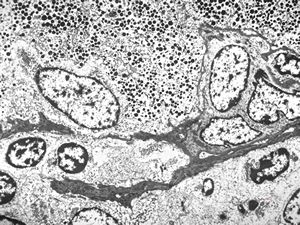

M, 62y. | pheochromocytoma